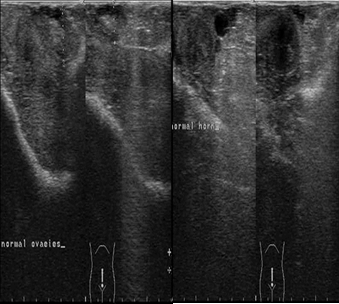

The ultrasonographic imaging of the uterus and ovaries was performed daily 9th day postpartum then followed by examination twice weekly until the 21st day postpartum. The ultrasound examination showed normal uterine involution and no abnormal secretions in the uterus (Figure 2).

Figure 2.Ultrasonographic image of ovaries (a) and uterine horn (b) at the 9th day postpartum in female camels, the image illustrate normal ovarian structure with no ovarian cysts and the uterus showed normal uterine involution and no abnormal discharges.

Ultrasonographic image of ovaries (a) and uterine horn (b) at the 9th day postpartum in female camels, the image illustrate normal ovarian structure with no ovarian cysts and the uterus showed normal uterine involution and no abnormal discharges.

The serum progesterone level decreased sharply after parturition during the 1st, 3rd and 9th days postpartum, which is considered physiological decrease due to the lysis of corpus luteum of pregnancy and the drop of placenta which is considered another source of progesterone to maintain pregnancy, in addition the lactation status significantly affects on serum progesterone level16. It was proved that the plasma concentration of progesterone was increased by the 5th days after mating and remained high throughout most of pregnancy, and it starts to decline by the 2nd weeks before parturition3, 17. In addition, the low level of progesterone detected in the 1st day postpartum concur with previous studies during postpartum females in camels18 and other species19. Similar changes in the hormonal levels were observed during pregnancy, parturition and postpartum in llama20, 21. The ultrasonographic examination was performed twice weekly during the postpartum period starting from the 3rd day postpartum until the 21st day postpartum, there was normal uterine involution and no abnormal secretions in the uterus, this was in agreement with previous studies by Abu-Seida22, Derar, Ali23, who found that the uterine involution was completed in female camels from 25th until 30th days postpartum.